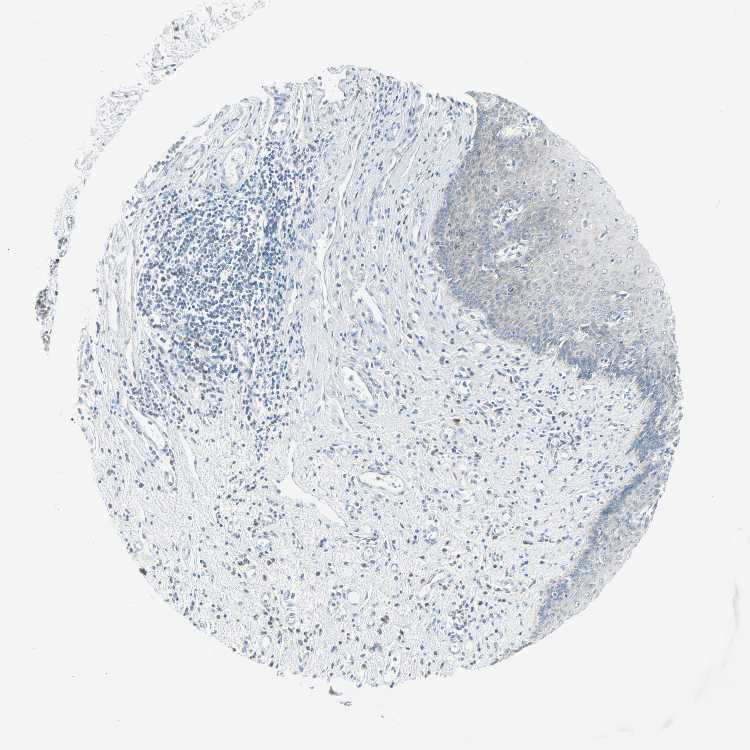

ESOPHAGUS - Antibody stainingi

Antibody staining in the annotated cell types in the current human tissue is reported as not detected, low, medium, or high, based on conventional immunohistochemistry profiling in selected tissues. This score is based on the combination of the staining intensity and fraction of stained cells.

Each image is clickable and will lead to virtual microscopy that enables deeper exploration of all samples and also displays staining intensity scores, fraction scores and subcellular localization as well as patient and tissue information for each sample.

Antibody HPA007401

Squamous epithelial cells Not detected